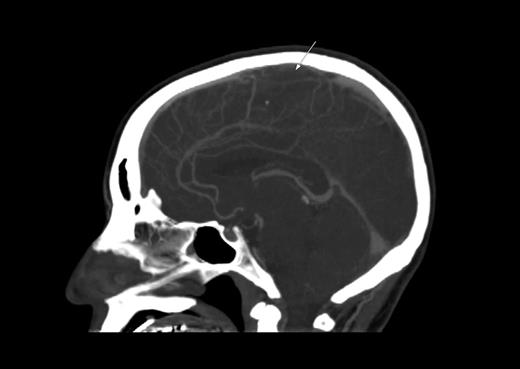

A 35-year-old man with B-lineage ALL is treated with a standard ALL protocol.55 On day 17 of induction, Escherichia coli L-asparaginase (L-ASP) is started at a dose of 10 000 units/day in combination with prophylactic subcutaneous low molecular weight heparin (LMWH). Pretreatment thrombin time, partial thromboplastin time, fibrinogen, and D-dimer levels are normal. On day 9 of L-ASP, he presents with generalized seizure, right-sided limb weakness, and slurred speech. CT scan discloses extensive sagittal sinus thrombosis (Figure 2). L-ASP treatment is discontinued and full dose heparin is initiated. There is no evidence of inherited thrombophilia.

CT scan. Sagittal plane demonstrating sagittal sinus. The arrow indicates the filling defect corresponding to sagittal sinus thrombosis.

We treat CNS thrombosis with full-dose heparin coupled with intensive cryoprecipitate and platelet transfusion support. Sagittal sinus thrombosis is often accompanied by increased intracranial pressure and secondary hemorrhagic infarct. We continue heparin, even in the presence of such hemorrhage with blood product support and frequent CT/MRI monitoring, because the primary event is thrombosis. Importantly, for the same reason, L-ASP may be resumed at lower doses if toxicity was not greater than grade 3 and completely resolved.59,65